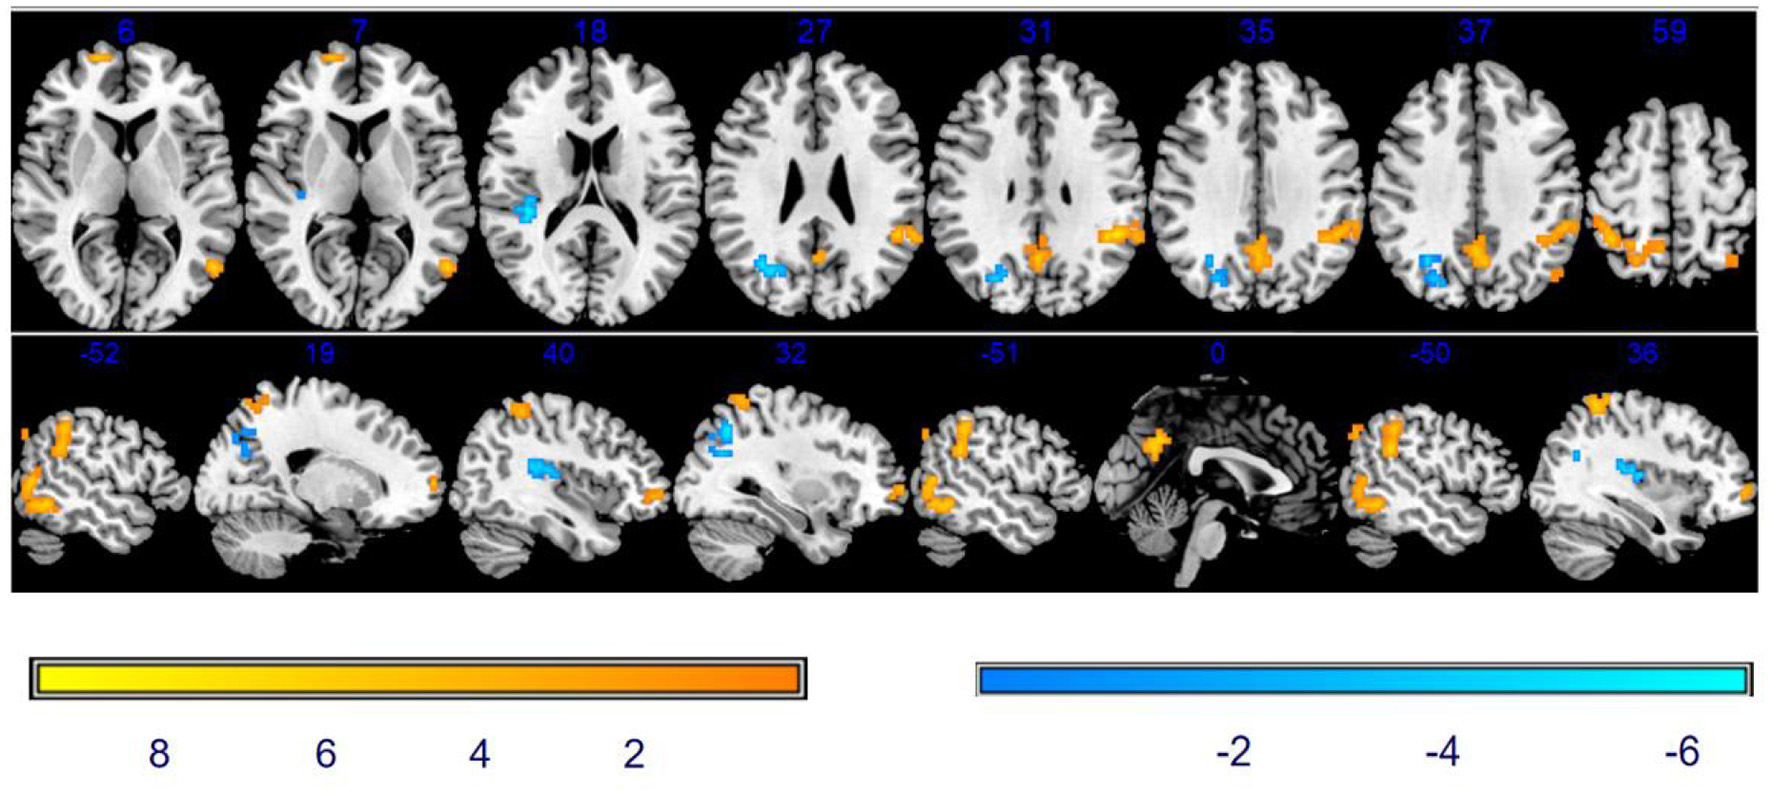

Comparison of DC between baseline and after stSCS

As shown in Table 3 and Figure 4, there was a significantly increased DC in the vast region of the left middle temporal gyrus, right rolandic operculum, left supramarginal gyrus, right supramarginal gyrus, right precentral gyrus (PCG), left precuneus, and left inferior parietal after stSCS.

Figure 4

Significant differences in DC between baseline and after stSCS in axial and sagittal slices. The warm colors indicate higher DC values at baseline and after stSCS (p < 0.05). Brain images are presented in radiology convention (the left of the figure represents the right side of the patient's brain and vice versa).